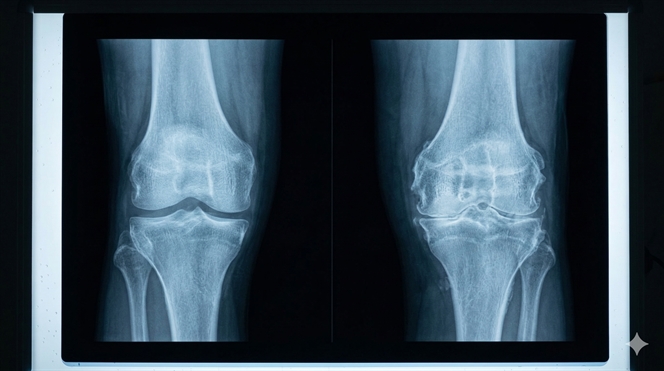

Hình ảnh X-quang: Khe khớp gần như biến mất hoàn toàn, hai đầu xương chạm sát vào nhau (xương chạm xương), gai xương lớn đâm vào các mô mềm xung quanh gây đau đớn cực độ.

Hình ảnh X-quang cho thấy sự tiêu biến hoàn toàn của khe khớp trong thoái hóa khớp giai đoạn cuối.